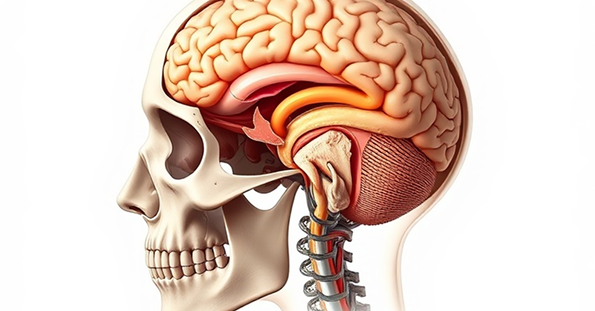

Understanding Head

Injuries

Head injuries can have serious long-term effects on cognitive function and quality of life. Our experienced team helps victims understand their rights and pursue maximum compensation.

Expert Care

Specialized medical support

Legal Protection

Full compensation claims

Brain Injury Impact

Brain injuries can have profound effects on victims and their families, impacting daily life and overall well-being. Understanding your legal options is crucial in seeking compensation for these life-altering injuries.

Brain Injuries

Traumatic brain injuries can have devastating long-term effects on cognitive function, memory, and quality of life.